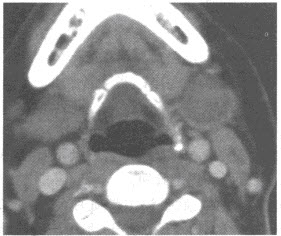

男,50岁,有吸烟史,自觉左侧颌下肿物1个月余。CT增强扫描如下图,应诊断为()

A:左侧颌下淋巴结转移

B:左侧颌下神经鞘瘤

C:左侧颌下淋巴结结核

D:颌下腺多形性腺瘤

E:颌下腺腺淋巴瘤